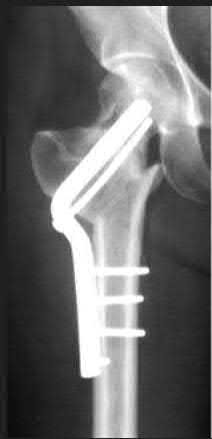

A 76-year-old male community ambulatory presented to clinic complaining of pain in the left groin that has been persistent for the last 8 months. Radiographs obtained from clinic are seen in Figure A. You suspect a femoral neck nonunion and obtain a CT scan which confirmed it. Which of the following statements is true?

A total hip arthroplasty (THA) after nonunion of a femoral neck fracture would provide the best long term outcomes in a 76-year-old male who is a community ambulator.

After nonunion of a femoral neck fracture, hemiarthroplasty and THA are good salvage option for the physiologically older patients. When deciding between these two options, THA is better for active and cognitively intact patients. THA is also indicated in patients with radiographic evidence of degenerative disease about the acetabulum. Hemiarthroplasty is advocated for patients who are older and less active.

Yang et al. retrospectively investigated the risk factors for nonunion in patients treated with cannulated screws. They reviewed 202 patients who had femoral neck fractures and were treated with internal fixation with cannulated screws. They identified that triangle configuration, displaced fracture, borderline or unacceptable reduction, and increased screw shaft subchondral purchase over the femoral neck were all risk factors for nonunion after internal fixation.

Inverted triangle configuration was found to increase rate of union.

Archibeck et al. retrospectively reviewed the outcomes of 102 THAs after failed internal fixation for a hip fracture (including both femoral neck and intertrochanteric). They concluded that the conversion of failed hip internal fixation has elevated risks compared to a primary THA, however, it may still be successful. The biggest concern for these patients postoperatively are periprosthetic fracture and dislocation.

Figures and Illustrations:

Figure A is an AP pelvic radiograph demonstrating a nonunion of a femoral neck fracture after suboptimal fixation with 3 cannulated screws in a triangle configuration.

Illustration A is an AP radiograph of the left hip in this patient following conversion to THA.

Illustration B is a radiograph demonstrating a valgus osteotomy. Illustration C shows an example of a femoral neck nonunion with varus malreduction.